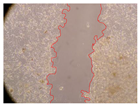

| 2 h | 8 h | 12 h | 24 h | |

| Control | ![]() | ![]() | ![]() | ![]() |

| Samples | 0 h | 2 h | p-Value | 8 h | p-Value | 12 h | p-Value | 24 h | p-Value |

|---|---|---|---|---|---|---|---|---|---|

| Control | 3.8 | 3.79 | - | 3.13 | - | 2.93 | - | 2.65 | - |